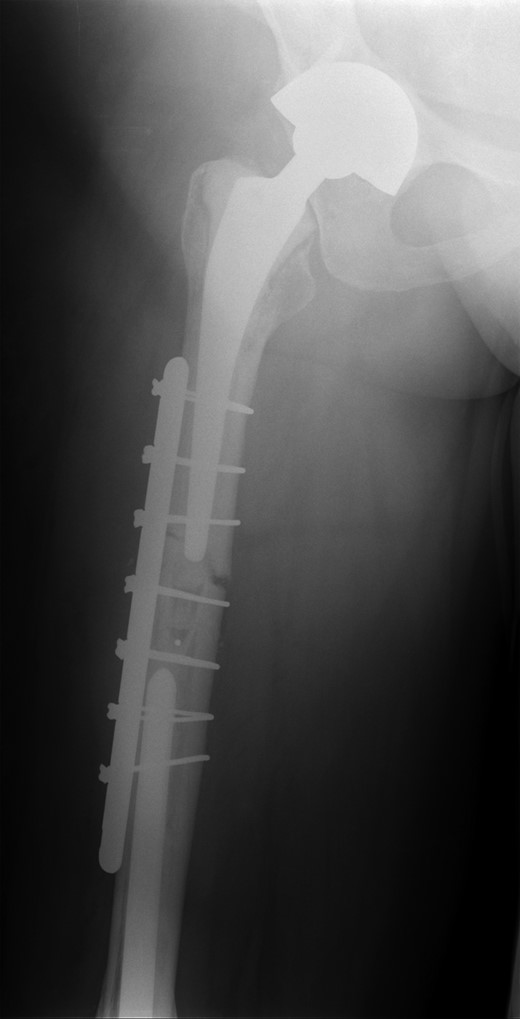

The operation was carried out by the senior author and the customized distal femoral prosthesis was successfully cemented over the pre-existing internal proximal femoral replacement (Figs 6 and 7).

Retained proximal femoral component with new custom-made cement-linked distal femoral prosthesis visible in lower half of the image.

New custom-made distal femoral prosthesis cement-linked to original salvage proximal femoral component visible in upper half of the image.